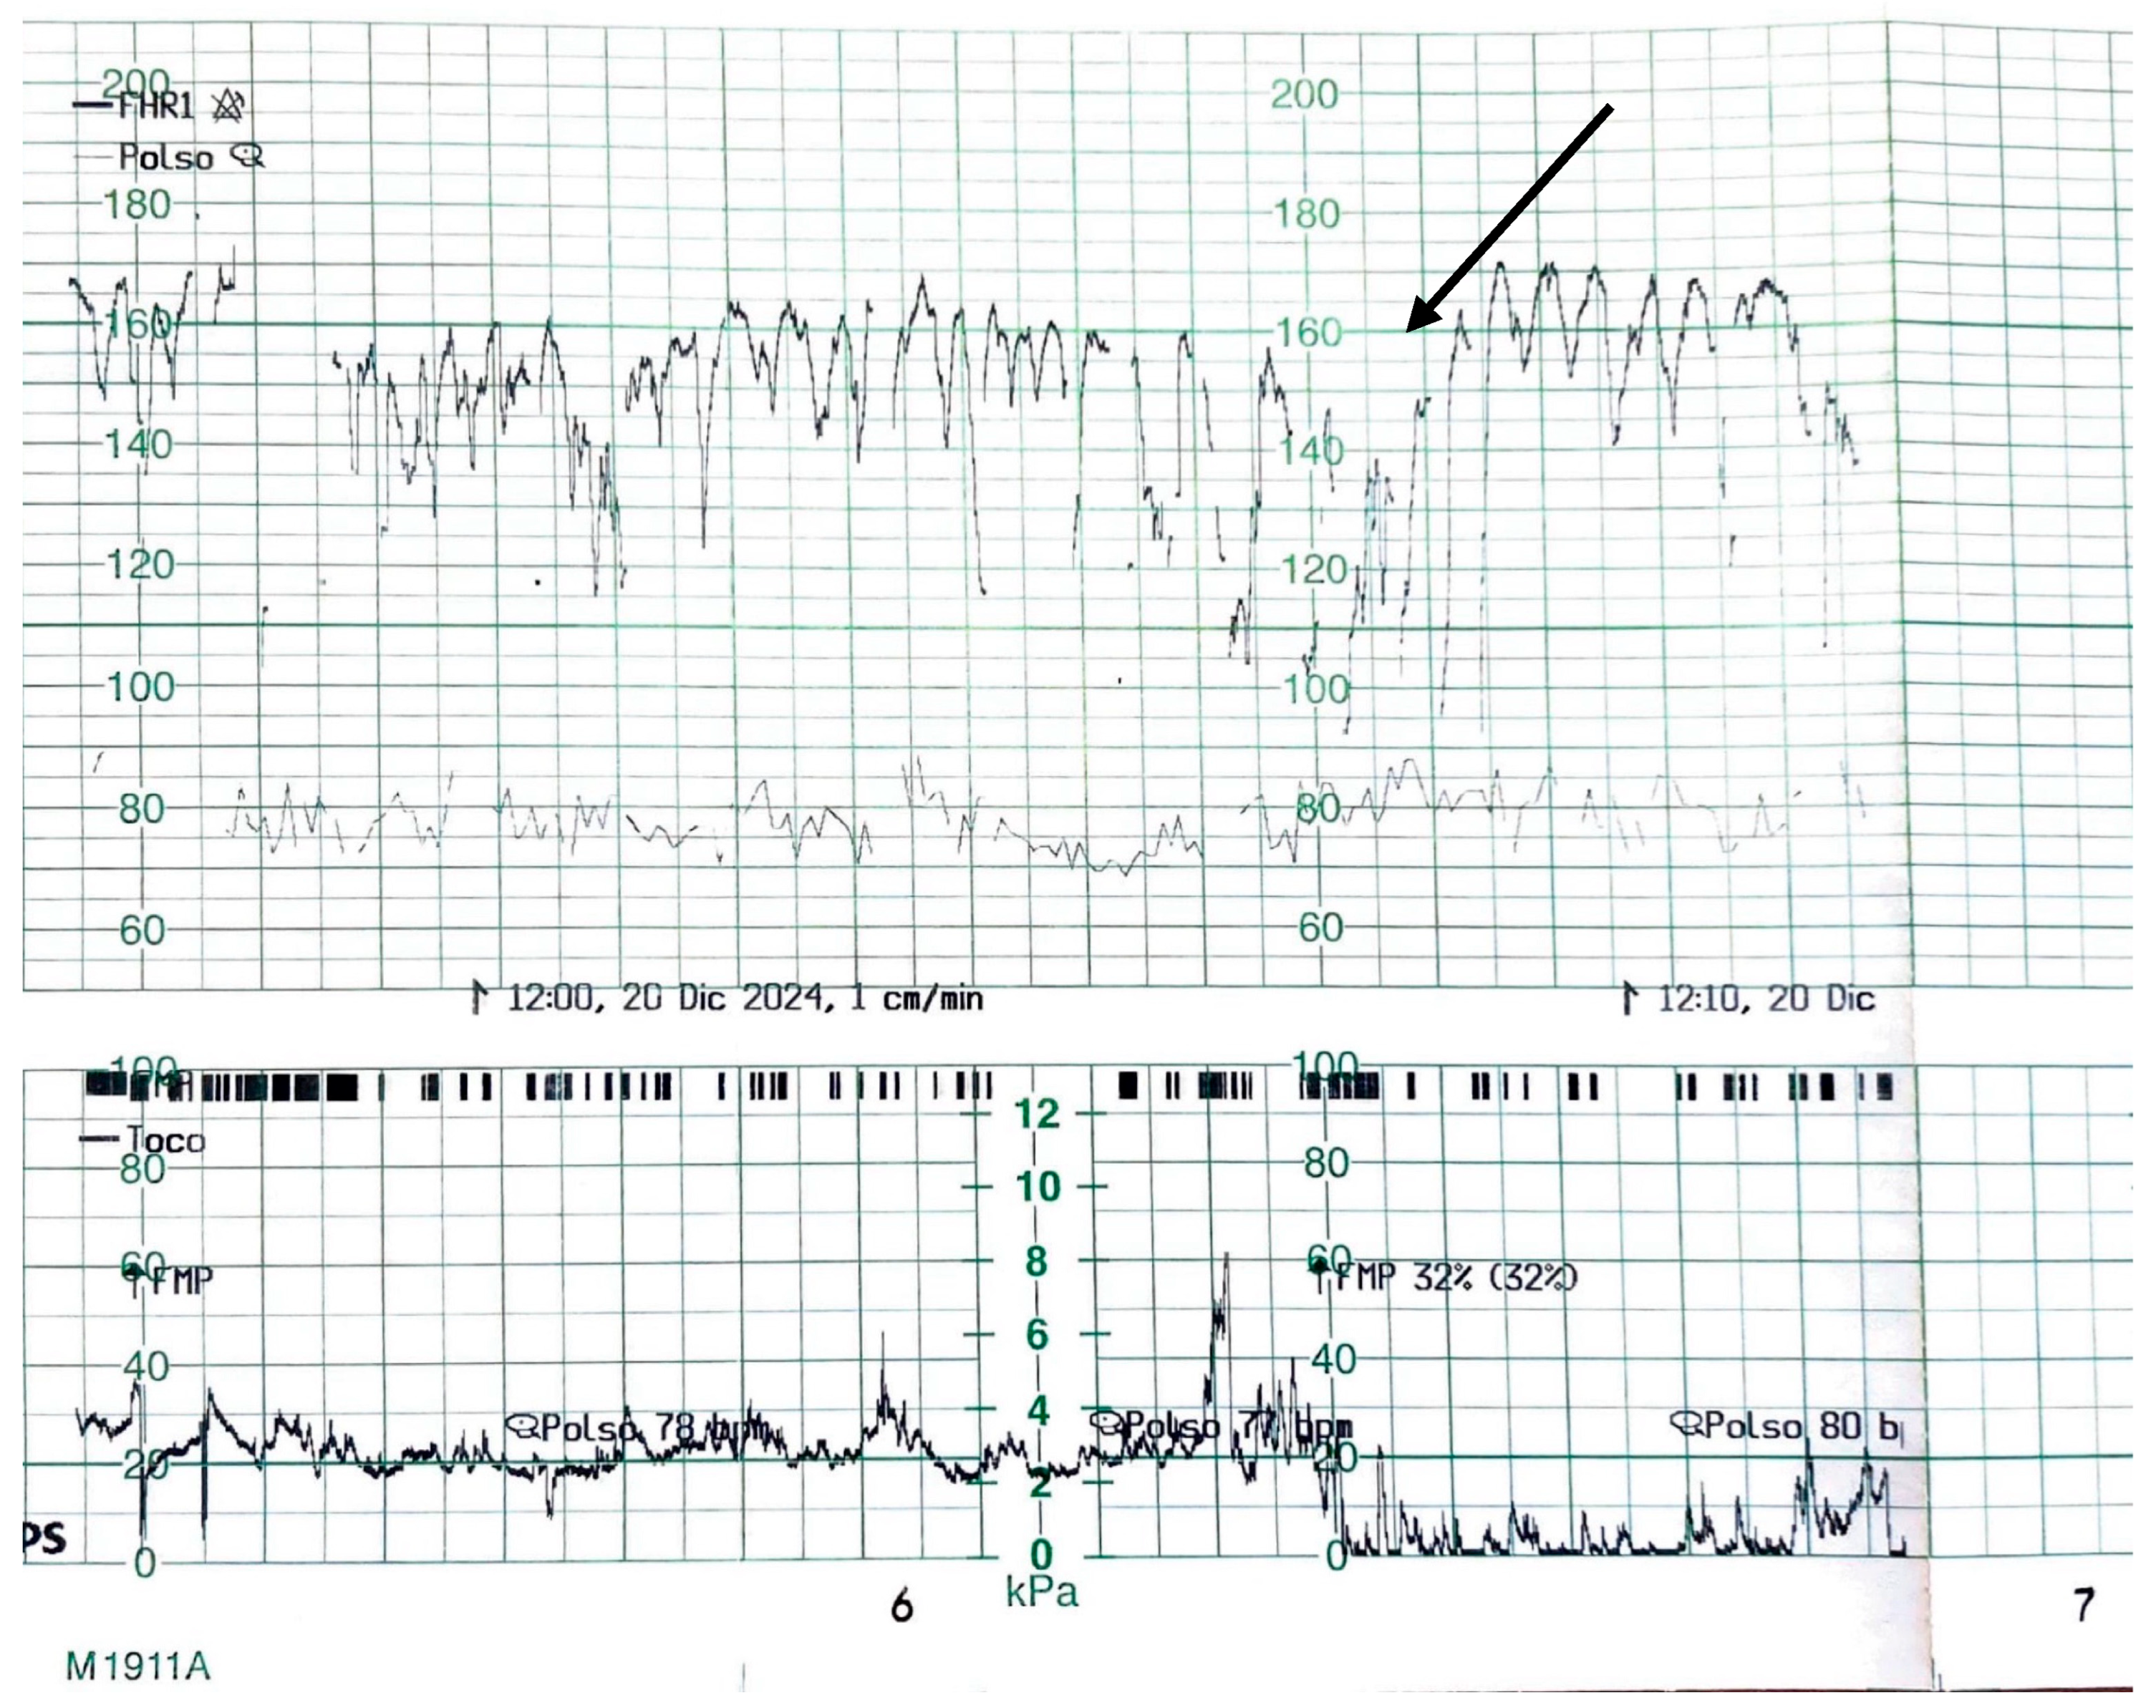

Physical examination revealed normal maternal vital signs, absence of fever, no foul-smelling vaginal discharge, and no uterine tenderness. The amniotic membranes were intact, and the obstetric examination showed an unfavorable Bishop score [16]. Maternal blood pressure was 110/75 mmHg, maternal blood glucose 89 mg/dL, and the use of any form of medication by the mother, except iron and vitamins, was not reported. As shown in Figure 1, the admission cardiotocography (CTG) displayed a “zigzag pattern” [15] in the absence of uterine contractions. Given the findings, the decision was made to proceed with an emergency cesarean section.

The CTG tracing showed a baseline fetal heart rate fluctuating between approximately 130 and 170 beats per minute, with recurrent, abrupt oscillations exceeding 25 bpm in amplitude. These fluctuations were irregular in both frequency and morphology and persisted for more than one minute. No uterine contractions were observed in the lower panel, confirming that the variability was independent of contractile activity. The baseline variability appeared markedly increased, without sustained accelerations or decelerations, and the tracing exhibited an overall pattern of heightened, disorganized oscillations around the baseline.

Figure 1. Admission CTG before the emergency cesarean section. The arrow in the figure highlights the characteristic ZigZag pattern.